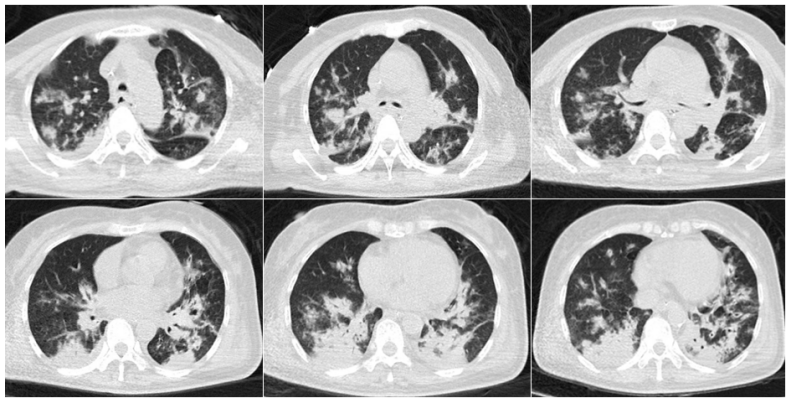

糖皮质激素的使用在其他病种中也被认为是IPA的危险因素,在重症流感中也不例外,有研究表明入ICU前系统性应用大剂量糖皮质激素是继发IAA的独立危险因素。除了重症流感,患者可能还会合并其他基础疾病,尤其是可以影响患者免疫状态的基础疾病,可能也是IAPA的危险因素。病例1::男,15岁,学生;主因“发热、干咳16天,加重伴呼吸困难8天”入院。既往体健,无基础病。入中日医院MICU时间为2018年1月16日,死亡时间为2018年1月26日。患者16天前(2017年12月30日)出现发热,体温39.0℃,伴干咳、咽痛。8天前(2018年1月7日)出现呼吸困难。血气分析示Ⅱ型呼吸衰竭,WBC 24.1×109/L,NE% 90%,PCT 3.3 ng/ml。不断升级抗细菌治疗,效果不佳:头孢曲松→亚胺培南、阿奇霉素、利奈唑胺。7天前(2018年1月8日)确诊乙流,加用帕拉米韦+奥司他韦。2天前(2018年1月13日):血GM试验测值增高,痰培养烟曲霉,诊断IAPA,加用伏立康唑。2018年1月15日转入中日医院呼吸与危重症医学科MICU。2018年1月8日胸部CT(起病1周余)提示气压伤非常严重,以及沿气道分布的斑片和小结节。此时的影像学提示曲霉感染已经显而易见(图1),但尚未得到病原学证据的支持,因此外院当时并未予抗真菌治疗,延迟抗真菌治疗也是导致患者预后不良的重要原因之一。1月15日(转入中日医院MICU后)气管镜检查,镜下可见气道狭窄和黏膜充血水肿均较明显,表面大量白苔,触之易出血(图2)。此时除了曲霉感染,BALF病原学还发现合并了CRAB感染。患者影像学快速进展,1月15日胸部CT显示双肺弥漫性沿支气管血管束分布的结节影、斑片影、厚壁空洞及片状实变(图3)。1月22日胸部CT显示双肺病变明显进展,结节、斑片融合为大面积实变影(图4)。最终患者因CRAB血流感染导致感染性休克,后期又并发脓毒性心肌病,最终去世。病例2::女,65岁,退休。间断干咳伴发热10天,加重伴呼吸困难4天。既往2型糖尿病史35年,使用精蛋白生物合成人胰岛素注射液(预混30R)治疗,血糖波动在7~8 mmol/L。患者入ICU时间为2018年2月4日,出ICU时间为2018年4月19日。10天前(2018年1月25日)“感冒”后出现干咳,伴发热,体温最高37.8℃。7天前(2018年1月28日),血常规:WBC 12.49×109/L,NEU% 87.5%,LYM% 7%,予莫西沙星。1月30日复查血常规:WBC 23.88×109/L,NEU% 91.5%,LY% 4.6%,调整抗生素为头孢噻肟+莫西沙星。4天前(1月31日)呼吸困难加重,SpO2(未吸氧)88%,复查血常规:WBC 37.04×109/L,NEU% 93.7%,LYM% 1.7%,PCT 1.79 ng/ml,痰涂片可见真菌孢子及菌丝。3天前(2月1日)咳痰费力,SpO2降至71%,开放气道吸痰过程中心率降至32次/min,立即心肺复苏,气管插管球囊辅助通气,约12 min患者自主心率恢复,接呼吸机辅助呼吸,经气道可吸出大量黄色黏痰,痰流感病毒核酸阳性。1月31日胸部CT示:沿支气管血管束分布的斑片和实变影(图5)。气管镜下可见充血、水肿,曲霉特征性假膜相对较少(图6)。

2月13日复查胸部CT(抗真菌治疗14天)显示影像学较前好转(图7)。患者病程中也经历了院感、肺外脏器支持等,病情最终好转出院。(1)一般情况:流感合并曲霉感染患者, 男性居多, 年龄大, 基础病情更加严重, 伴有免疫抑制因素(例如: 肿瘤、免疫抑制剂、激素)。(2)起病时间较早(入ICU早期),入ICU至IAPA诊断的平均时间<72小时(3天),短于COVID-19相关肺曲霉病(CAPA)4~13天,流感至IAPA诊断时间为(13±7)天。(3)临床症状/体征不典型:IAPA的临床表现无特异性,可表现为发热、咳嗽、呼吸困难、病情加重且对现有治疗无效。部分患者可能出现咳黑褐色痰或咯血,并且有致死性大咯血风险。CAPA和COVID-19相关肺毛霉病(CAPM)患者发展为重症需入住ICU的比例更高。此外,患者常合并呼吸衰竭/ARDS、急性肾损伤(AKI)、感染性休克。(4)实验室及影像学检查:实验室检查有一项比较重要的提示,IAPA患者可能会因为炎症反应强烈而导致WBC非常高,但PCT一般不会明显升高,淋巴细胞常明显降低。影像学表现有其特点(如前所述)。(5)独立危险因素:ICU早期WBC明显增高(>10×109/L)、入ICU后应用激素、CT特征表现(多发结节、空洞)是IAPA的独立危险因素。但仍需大样本量、多中心的病例对照研究进一步验证。从上述两个病例可以发现,由于患者的症状、体征、实验室检查大部分不特异,且常被伴发的流感及混合的细菌感染所掩盖,因此IAPA的早期诊断较困难。微生物学依据是诊断IAPA的金标准,而在拿到微生物学证据之前,影像学和气管镜检查可以帮助我们寻找蛛丝马迹,在临床上具有重要意义及提示作用,有助于早期诊断。因此,熟悉其表现尤为重要。(1)微生物学证据:2020年欧洲医学真菌学协会/国际人类和动物真菌学学会(ECMM/ISHAM)发布的关于CAPA的定义及共识声明中提到的检测方法以及cut off值可供参考,包括:①BALF直接镜检阳性、BALF培养/PCR阳性,血GM/LFA>0.5,BALF-GM/LFA≥1;②血浆/血清/全血PCR阳性≥2次;③单次BALF PCR阳性且CT<36;④单次血浆/血清/全血PCR阳性,且单次BALF-PCR阳性(不要求CT值)。(2)CT表现:CT在IAPA的早期诊断中具有重要的提示意义。病变沿支气管血管束分布;合并曲霉感染患者有明显的气道受累,包括气道壁增厚、气道狭窄,以及树芽征;典型的病变性质是结节和斑片,空洞及新月征不多见,但有特异性;大片实变影也相对特异,且提示预后差。(3)气管镜下表现:气管镜也是一种非常重要的早期诊断IAPA的手段,可以发现气管镜下典型的假膜。除了观察气道病变的特点及范围,还可以获得高质量的下呼吸道标本,有助于提高真菌培养阳性率,获取及动态监测BALF-GM试验结果。此外,气管镜还能够进行痰液引流。对于气道病变非常严重或局限的患者,气管镜还可以进行气道内给药。值得一提的是,来自欧洲7个国家和美国以及中国台湾等地的29名专家提出了IAPA诊断专家共识,2023年已发表在Intensive Care Medicine 杂志上,将IAPA分为曲霉菌性气管支气管炎及侵袭性肺曲霉病,高度强调了气管镜的重要性,无论是气管镜镜下表现还是气管镜获取BALF标本进行GM试验或真菌培养都是共识中的重要条目,可能有助于IAA的早期诊断。